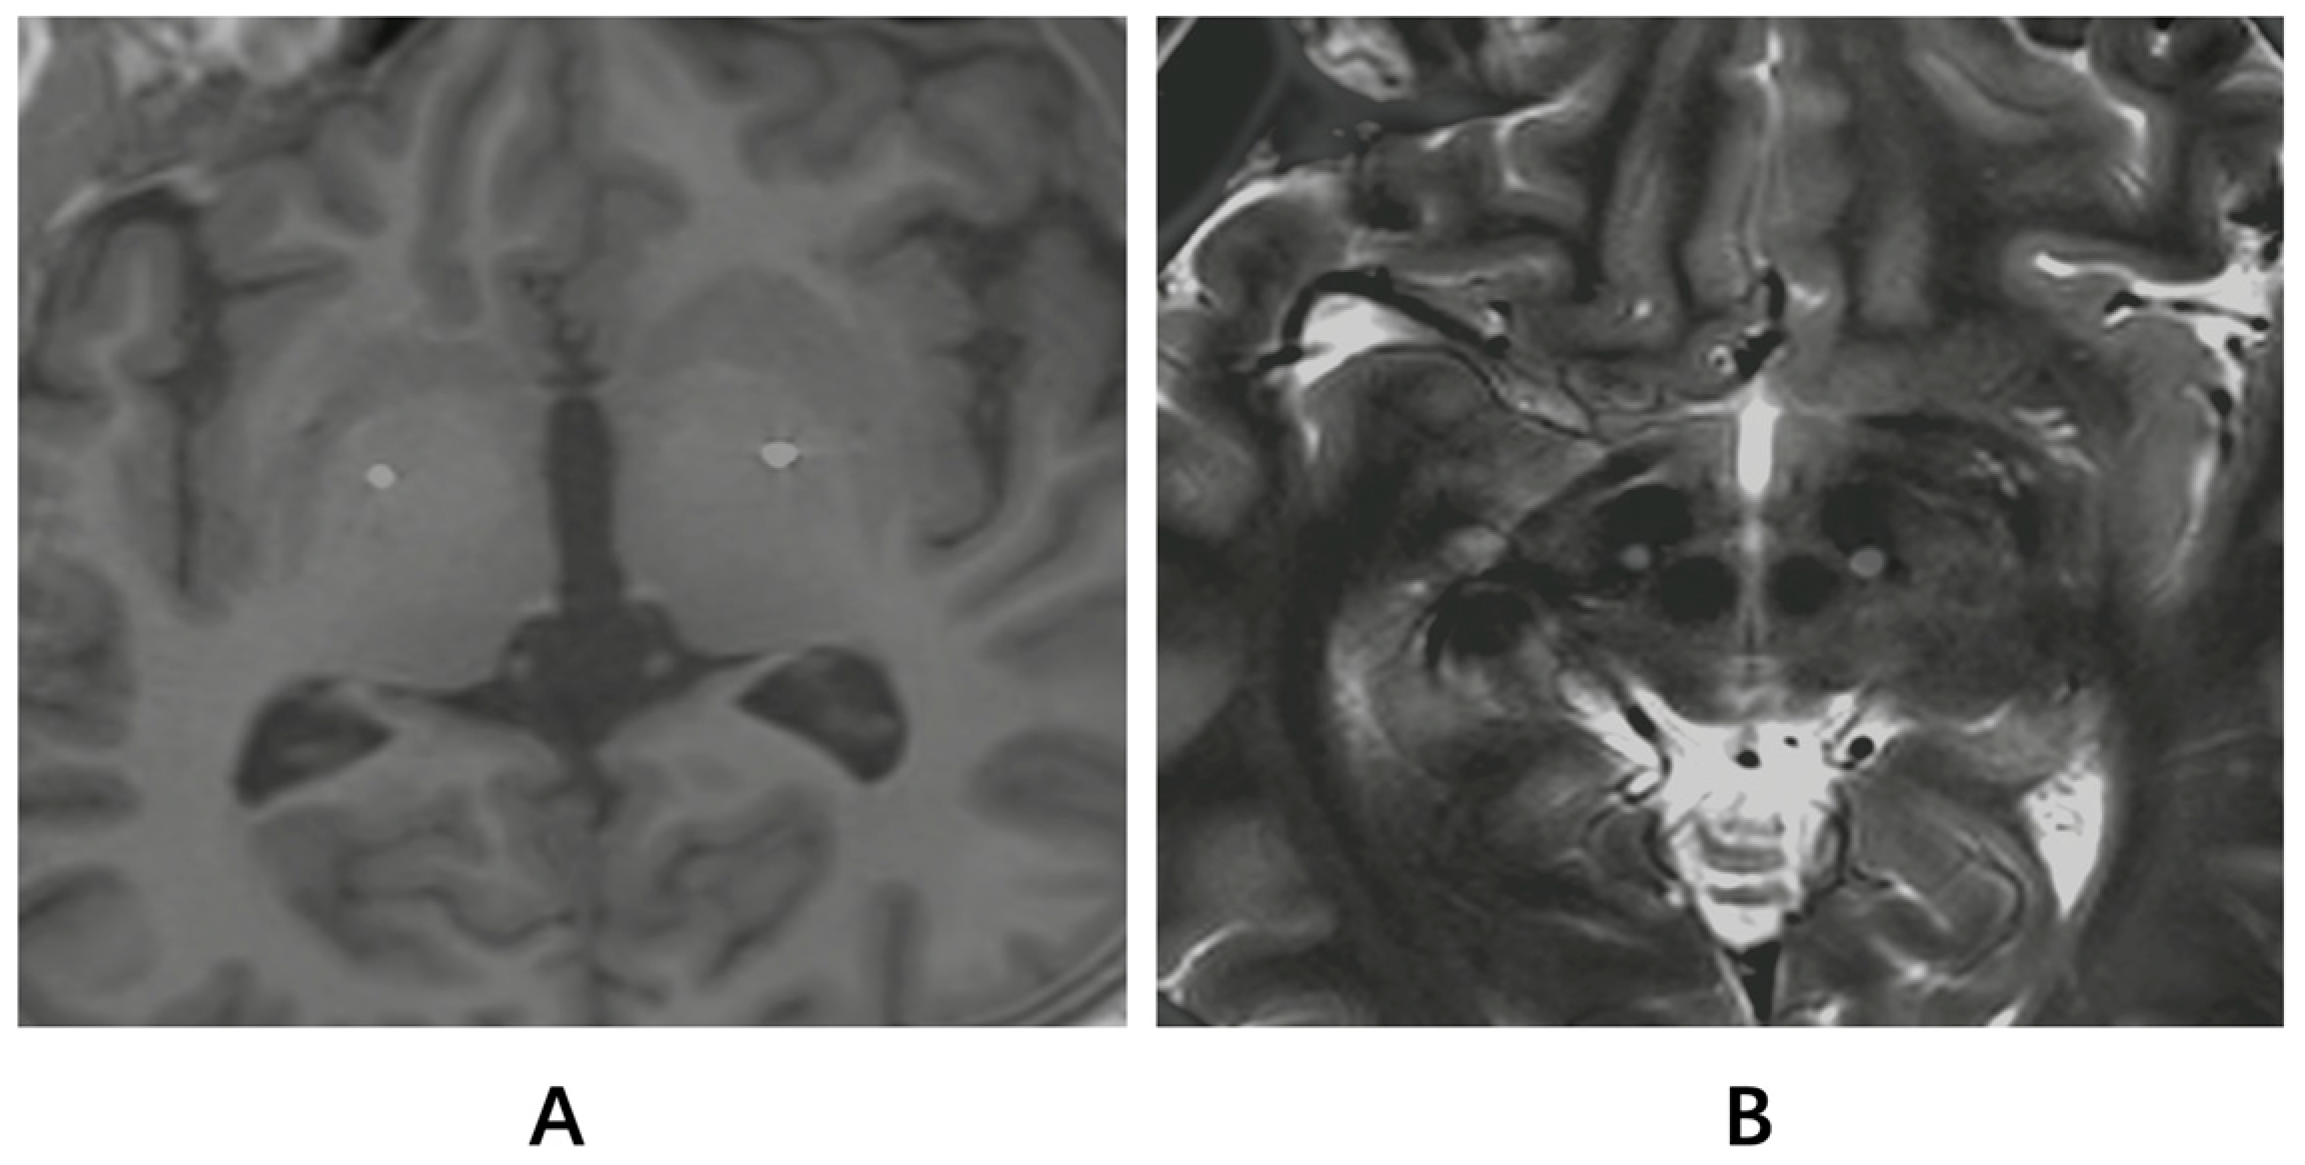

2.2. Treatment Procedure and Programming